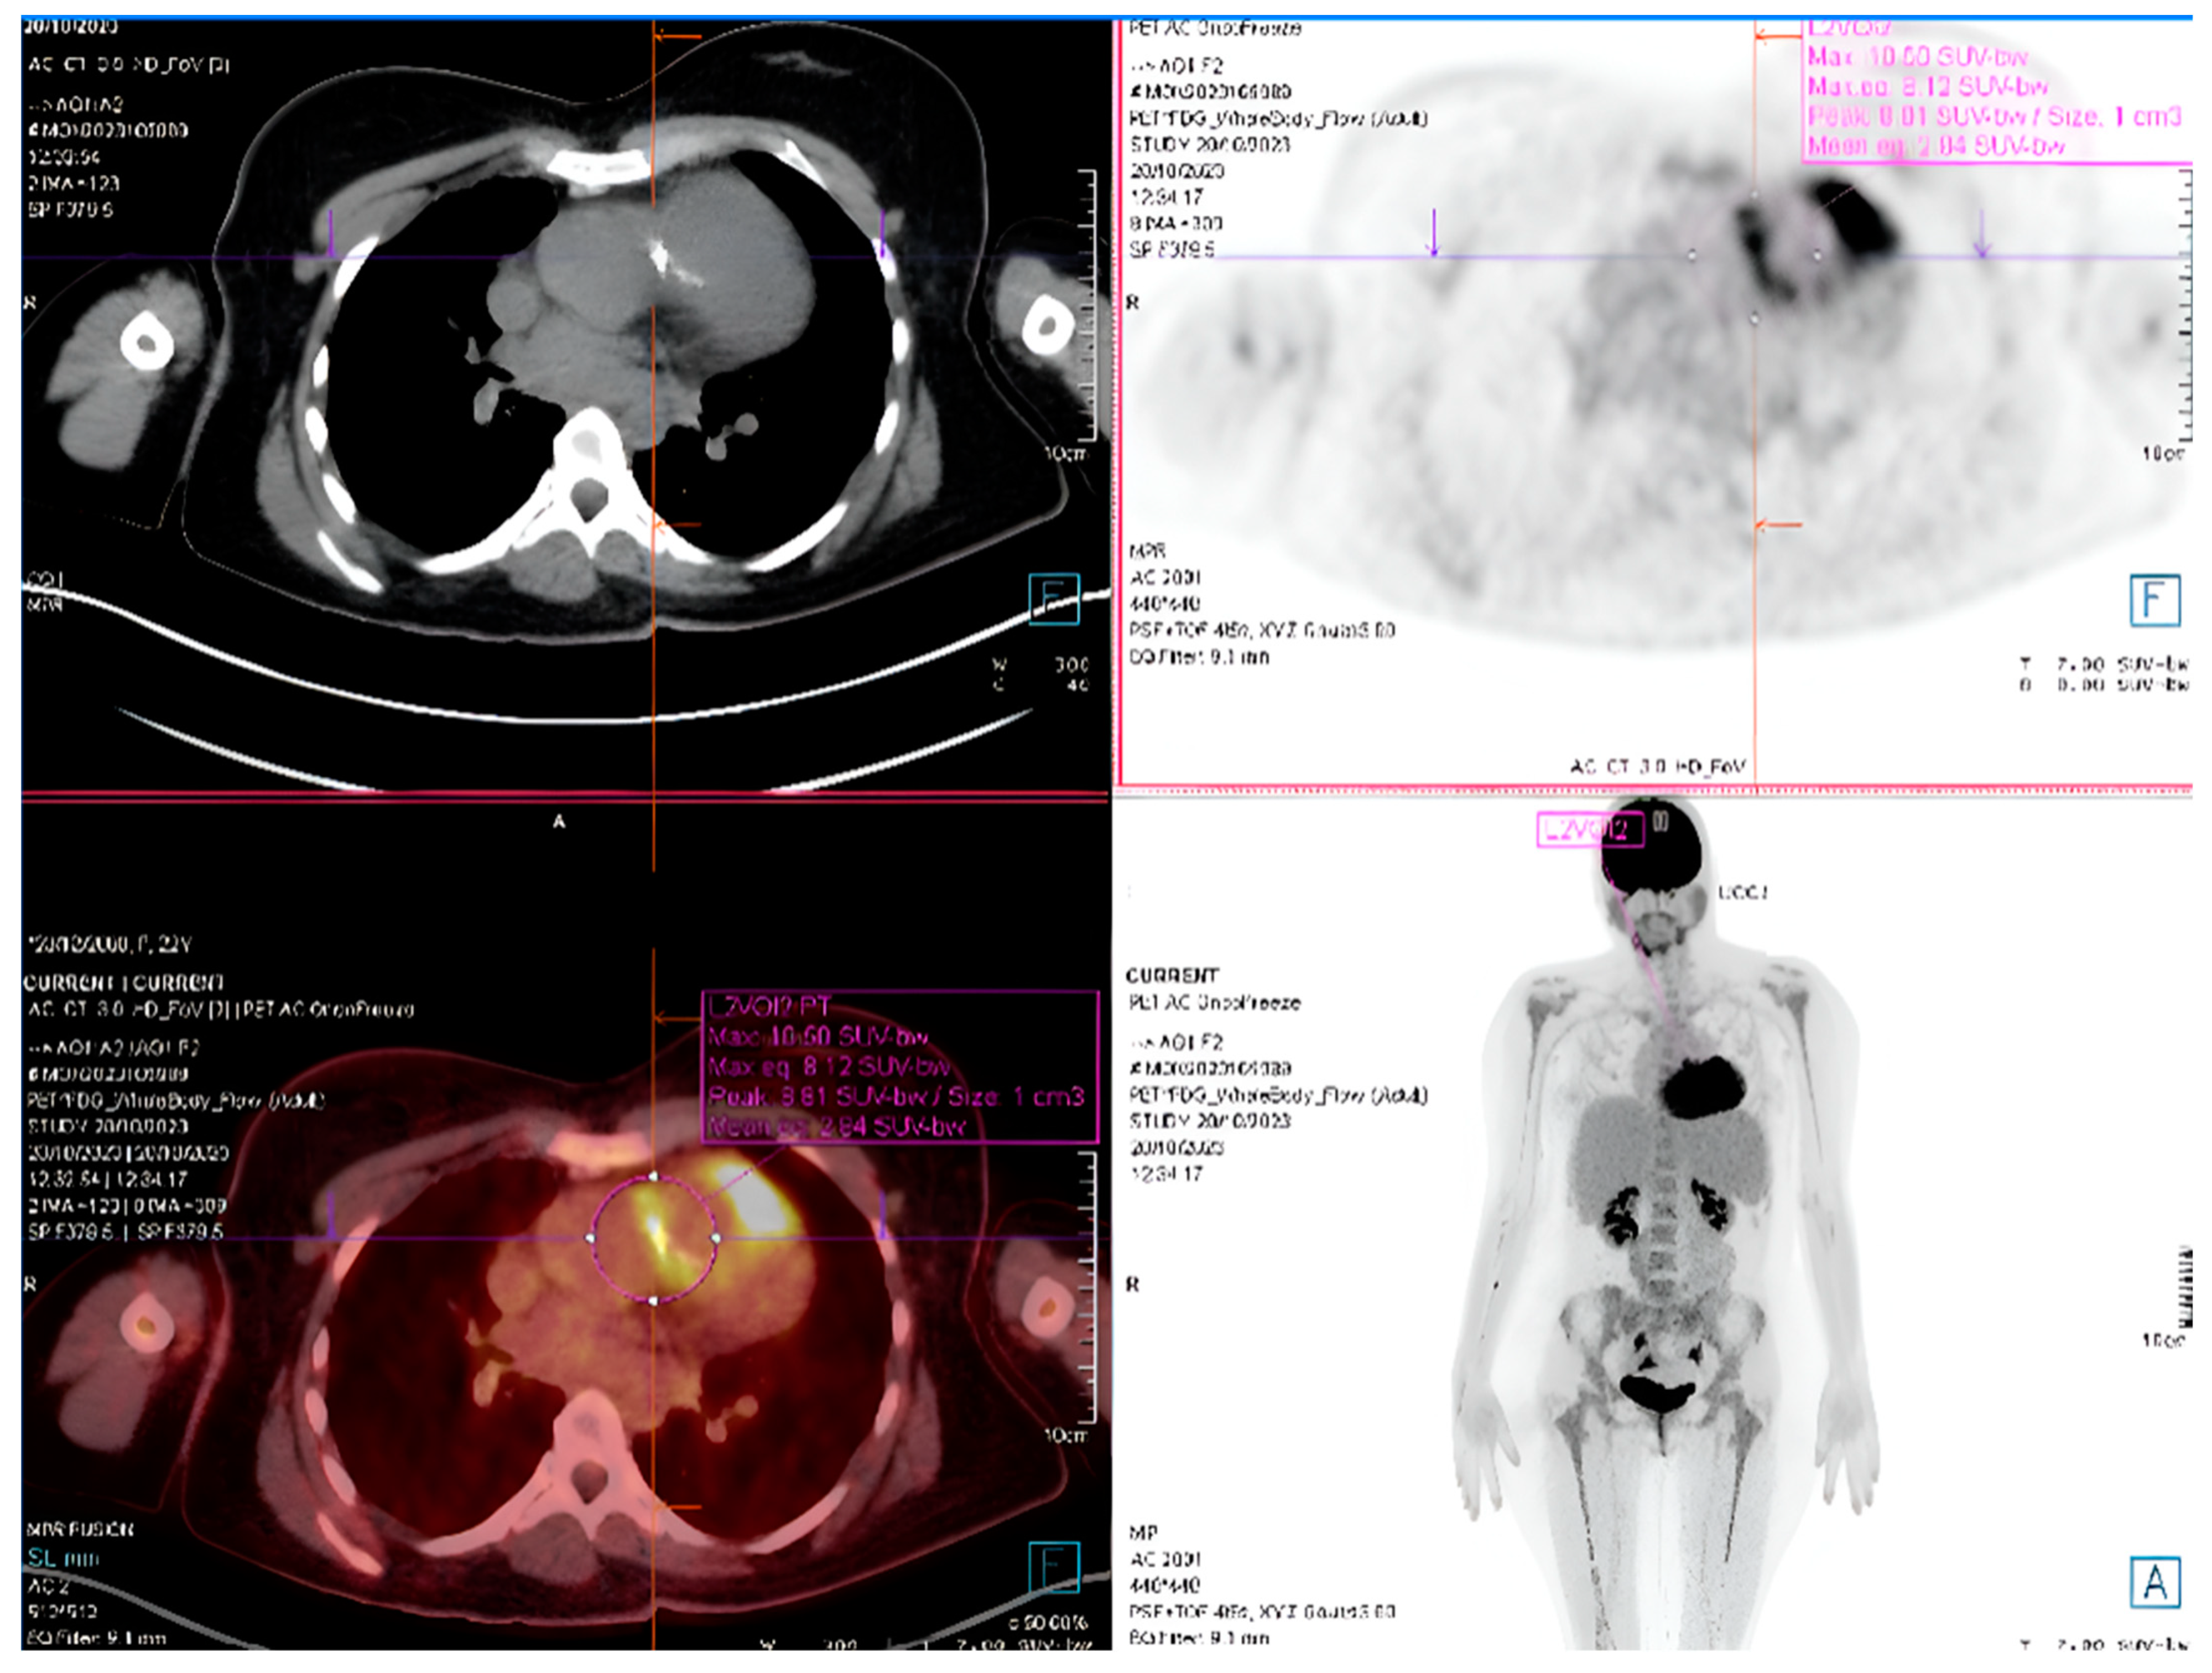

- Detecting Device-Related Infections: PET/CT is highly effective for evaluating infections involving prosthetic valves, pacemaker leads, and other intracardiac devices (Figure 7). It offers unmatched sensitivity in visualizing device pockets and lead tracks, helping differentiate sterile thrombi from infectious vegetations. This is critical in CHD patients, who frequently require surgical implants as part of their treatment.

- Enhancing Diagnostic Accuracy with the Duke Criteria: PET/CT significantly improves the sensitivity of the Duke Criteria for IE diagnoses, increasing it from 52 to 70% to 87–97%. By combining PET/CT findings with clinical and microbiological evidence, cases previously classified as “possible IE” can often be reclassified as either “definite” or “rejected”, reducing diagnostic ambiguity [27,98].

- Integration with CT Angiography (PET/CTA): When PET is paired with CT angiography, the resulting hybrid imaging achieves remarkable diagnostic precision. This combination leverages PET’s sensitivity for detecting metabolic activity in infected tissues and CTA’s detailed visualization of structural abnormalities. For instance, PET/CTA achieves a sensitivity of 91% and a positive predictive value of 93% for diagnosing infections involving prosthetic valves and intracardiac devices, significantly enhancing diagnostic confidence [99].